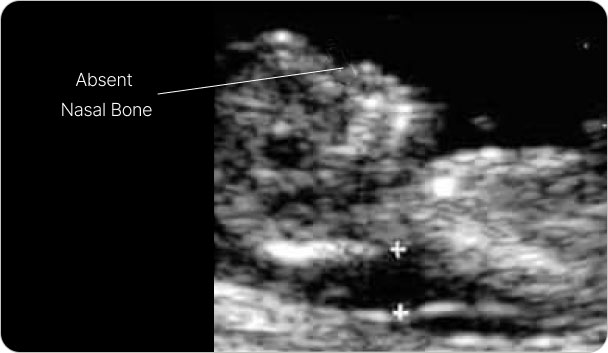

Nasal bone ultrasound scans

An absence of a fetal nasal bone, along with a thickened NT, is associated with a higher risk of Down syndrome.